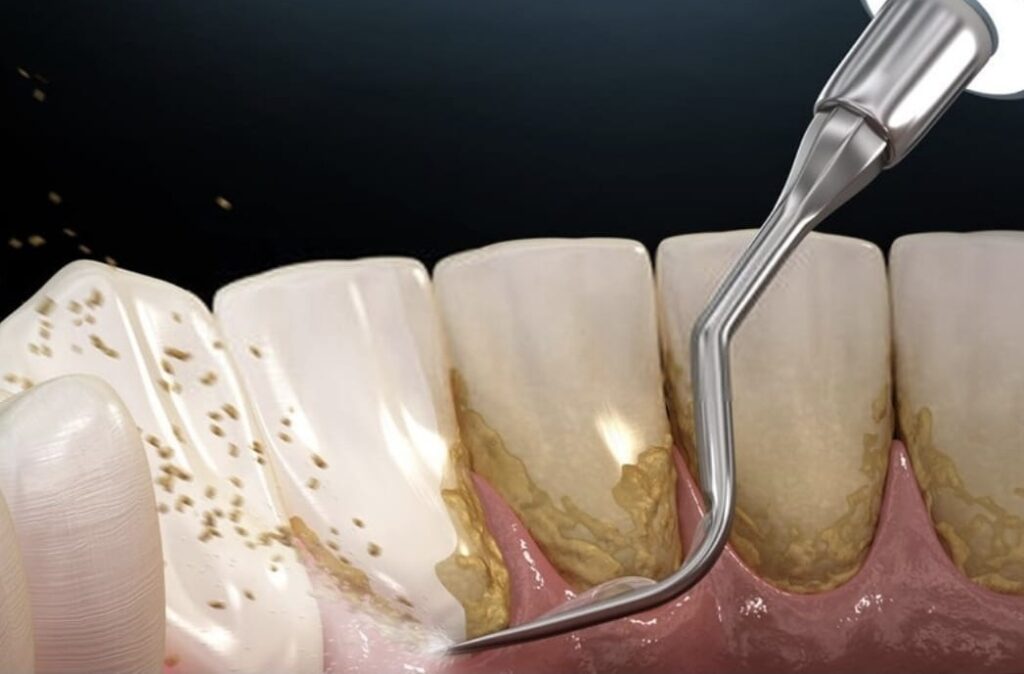

Eliminación del sarro y placa bacteriana

El cepillado diario es fundamental, pero no elimina el sarro acumulado. Las limpiezas profesionales ayudan a prevenir inflamación gingival, sangrado y pérdida ósea.